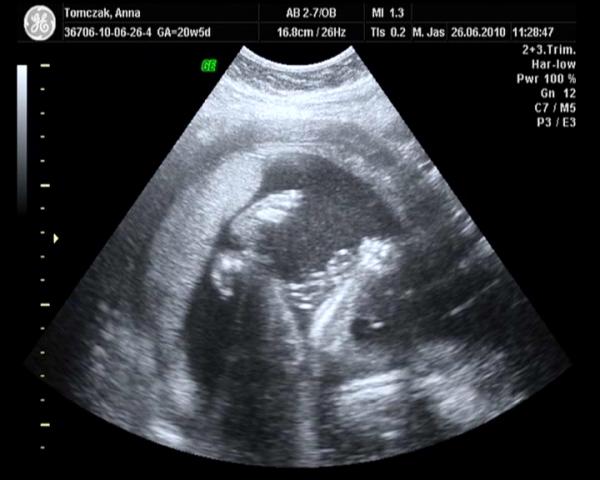

Dalam masa kehamilan, hampir semua ibu hamil mengetahui istilah USG, tetapi tahukah apa itu USG? Ultrasonografi atau yang biasa dikenal dengan sebutan USG, umumnya adalah teknik pencitraan medis yang digunakan untuk menggambarkan struktur, ukuran dan hampir setiap detail patologis dari otot, tendon, dan organ-organ internal lainnya. Dan seringkali juga digunakan untuk memvisualisasikan janin dalam kandungan.

Dalam penggunaannya untuk memvisualisasikan janin dalam kandungan, seringkali ibu hamil sangat menanti-nanti proses USG berikut. Selain dapat 'mengintip' wajah si kecil, ibu hamil juga dapat mengetahui kondisi dan jenis kelamin janin. Tetapi karena kebanyakan ibu hamil merasa takjub dengan pemandangan di layar USG, seringkali ibu hamil dan pasangan lupa menanyakan detail nya. Dan timbulah pertanyaan tentang istilah-istilah dalam cetakan USG nya.

USG atau Ultrasonografi seringkali digunakan untuk memvisualisasikan janin dalam kandungan. Dan dalam perkembangannya, terdapat beberapa macam jenis USG. Seringkali ibu hamil dan pasangannya bingung dalam menentukan jenis USG yang akan mereka pilih. Selain tarifnya yang berbeda, manfaatnya seringkali juga kurang diketahui. Berikut adalah beberapa penjelasan tentang macam-macam jenis USG :